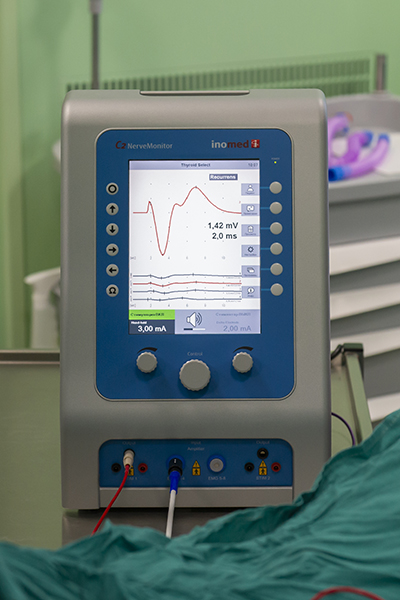

Начиная с 90-х годов XX века хирурги, оперирующие на щитовидной железе, стали использовать электромиографический контроль функции гортанного нерва. В последние 15 лет интраоперационный нейромониторинг претерпел ряд значительных изменений, в первую очередь связанных с внедрением неинвазивных методов регистрации сигнала с голосовых складок. Появилась возможность контроля и записи на цифровые носители таких нейрофизиологических параметров гортанных нервов, как амплитуда и латентность, и самое главное — хирург в ходе операции может оценить сохранность гортанного нерва, спрогнозировать функцию гортани в послеоперационном периоде и тем самым предотвратить двусторонний парез, изменив план операции.

Современные аппараты позволяют выполнять не только переменный мониторинг, но и постоянный. При переменном нейромониторинге у оператора нет возможности контролировать электрофизиологическое состояние гортанных нервов в промежутке между стимуляциями.

При постоянном мониторинге специальная клипса фиксируется к n. vagus (к блуждающему нерву, ветвью которого является тот самый возвратный гортанный нерв n. recurrens), данные по амплитуде и латентности доступны хирургу в реальном времени ежесекундно, что позволяет моментально отреагировать на нарушения проведения нервного импульса по нерву и предотвратить его повреждение, изменив хирургическую тактику. Это безопасный и надежный метод контроля электрофизиологического состояния гортанных нервов.

Профилактика нарушения функции гортанных нервов — одна из основных задач хирурга при проведении операции. В оперблок ГКБ № 52 для работы эндокринных хирургов закуплен нейромонитор — специальный аппарат для минимизации проблем с гортанными нервами. Он позволяет выявить нарушения проведения электрического импульса по нерву на первых секундах, осуществлять постоянный контроль функции гортанных нервов на протяжении всей операции и прогнозировать возможные проблемы.

Аппарат возбуждает нерв электромагнитным полем и вызывает прохождение импульсов по нерву, параметры прохождения электрического сигнала отображаются на мониторе.

Операция видеоэндохирургическая гемитиреоидэктомия с истмусэктомией справа (удаление одной доли щитовидной железы и ее перешейка) у пациента 40 лет с доброкачественным образованием щитовидной железы проводилась эндоскопическим методом: эндоскопическая техника дает несравнимую с открытыми операциями возможность визуализации всех анатомических структур. В начале операции, приблизившись к нервам, мы проверили «замкнутость цепи»: если нерв отвечает на стимуляцию, на мониторе появляется сигнал, по его амплитуде оценивается степень его травматизации, что позволяет внести коррективы в ход хирургического вмешательства. Так определяют наличие или отсутствие проблем, НЕ связанных с данной операцией. На рис. 2 сигнал от возвратного гортанного нерва. Далее в процессе операции, как я уже отмечал выше, можно в любой момент контролировать сохранность функции нерва.

Сигнал от возвратного гортанного нерва

Протокол постоянного мониторинга представлен двумя линиями и демонстрирует ежесекундные данные по величине амплитуды и латентности.